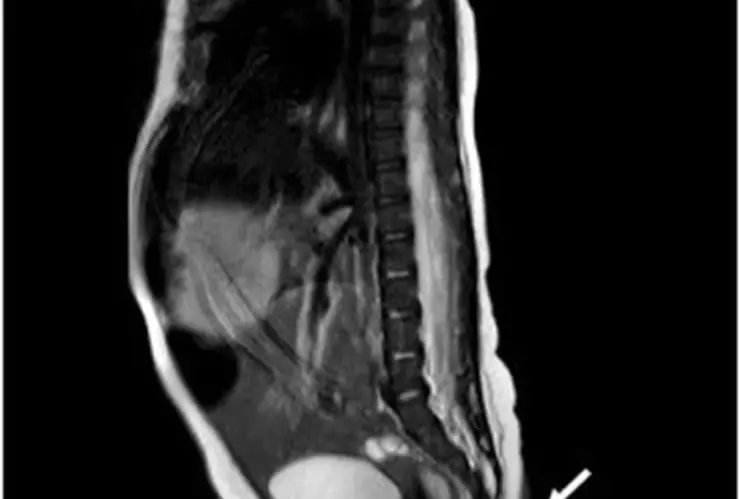

De acuerdo a los médicos, la cola del bebé tiene conexión con los nervios del cuerpo, esto lo confirmaron después de que procedieron a pellizcarla con una aguja, lo que provocará el llanto del bebé.

La cola tiene una medida de 5.7 cm de longitud y de entre 3 y 5 milímetros (mm) de diámetro, además de que se encuentra ubicada en la hendidura interglútea.

Finalmente señalaron que la cola de la bebé está cubierta de piel y tiene un poco de pelo fino, poco visible, pero esta no tenía movimiento alguno.

Los médicos lograron retirar su cola a la bebé cuando tenía dos meses y siguieron estudiando su extremidad. Al cabo de dos meses, la cola fue revaluada, encontrando que su extremidad adicional había crecido 0.8 centímetros, por lo que fue extirpada y la zona afectada reconstruida.